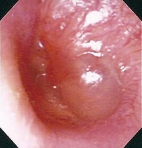

Eardrum during Crying Aged 1, male

Comment:

Dilation of relatively superficial vessels along the malleus was observed.

Images and comments by Dr. S. Takano <ENF-V2>